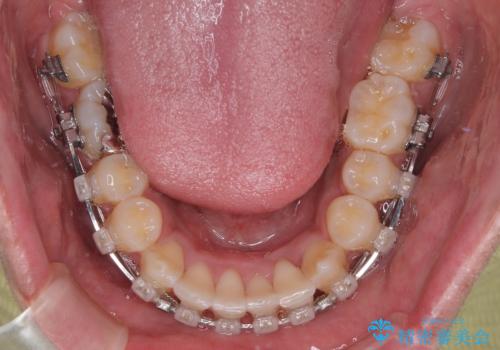

矯正治療後には気になっていた前歯をセラミッククラウンにし、自然な口元に仕上げることができました。